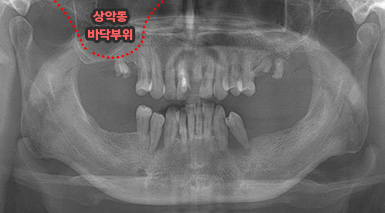

상악동 거상술

상악동 거상술 고난이도 뼈이식술 입니다.

청담네오플란트에서는 상악동 거상술을 비롯한

고난이도 임플란트 시술 노하우가 풍부한 치의학 박사

전문의가 직접 상악동 거상술을 시행합니다

상악동은 윗턱뼈 내부의 구조물로서 개개인에 따라 생김새가 다릅니다.

상악동의 바닥이 잇몸뼈 방향으로 많이 내려온 경우, 임플란트를 식립하기에

잇몸뼈가 부족하게 됩니다. 이러한 경우 상악동 내부로 뼈이식을 하는

상악동 거상술이 필요하게 됩니다.

B

A